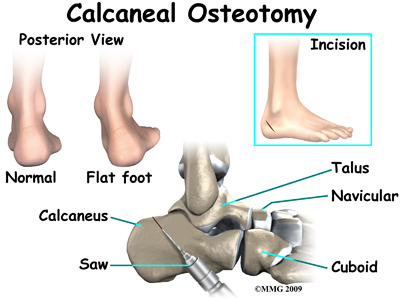

The most common surgical procedures used with this condition include arthrodesis (fusion), osteotomy (cutting out a wedge-shaped piece of bone), and lateral column lengthening. Lateral column lengthening involves the use of a bone graft at the calcaneocuboid joint, which helps restore the medial longitudinal arch (arch along the inside of the foot).

It's not clear yet from research evidence which surgical procedure works best for this condition. A combination of surgical treatments may be needed. It may depend on your age, type and severity of deformity and symptoms, and your desired level of daily activity. Studies do show, however, that long-term results of just reconstructing the posterior tibial tendon have been disappointing. As much as a 50 per cent failure rate has been reported which is likely because of the complexity of soft tissue interactions needed to maintain structural integrity of the foot. Reconstructing the spring ligament complex or using an osteotomy to lengthen the lateral side of the foot along with a tendon transplant is more likely to restore more normal foot and ankle movement with better results.